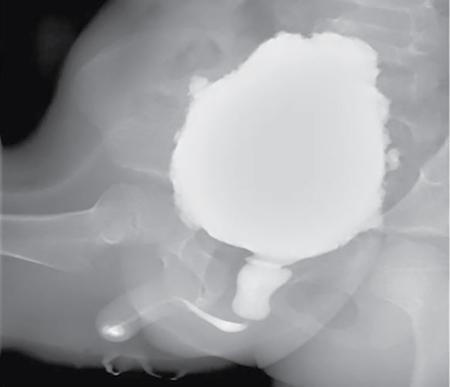

Anmol Bhatia, Kushaljit Singh Sodhi, Akshay Kumar Saxena Congenital as well as acquired anomalies of the bladder and urethra are a significant cause of morbidity in children. Various radiological investigations for imaging bladder and urethra include ultrasonography (US), voiding cystourethrography (VCUG) and intravenous urography (IVU), computed tomography (CT), magnetic resonance imaging (MRI) and contrast-enhanced voiding urosonography. In this chapter, we will discuss and illustrate a wide spectrum of congenital and acquired anomalies of bladder and urethral in children. Foetal allantoic stalk is the connection between the bladder dome and the umbilicus during the embryogenesis. Normally, it gets involuted by the second month of gestation. Depending on the degree of the persistence of this foetal allantoic stalk results in varying types of urachal remnants. The clinical presentation depends on the type of urachal remnant: Fluoroscopy is the best imaging modality for documenting the patency of urachus. However, there may be an underestimation of the exact length of the urachal remnant as inflammation occurring along the tract may block its lumen. CT and MRI are usually not needed for the detection of urachal remnants. However, urachal remnants are usually detected incidentally on CT scan done for other indications. Cystic or solid elongated tubular structure may be seen extending from bladder dome to umbilicus. A focal cystic lesion (Fig. 10.11.3) may be seen in the midline anywhere from bladder dome to umbilicus. In case the urachal remnant present with the symptoms, resection of the entire tract is warranted. Bladder diverticulum are localized outpouching from the bladder wall. They can be single or multiple of varying sizes. A male predominance is seen in comparison to females. It has been traditionally classified into four types: They can be incidentally detected or present with complications including recurrent UTI, urinary retention, incontinence, stone formation, VUR and bladder or ureteric obstruction. Bladder diverticulum should be differentiated from ‘bladder-ears’ in newborn male which is bilateral protrusion of bladder wall into inguinal ring. These are transient and disappear with growth. Appearance of diverticulum depends on cause, location, size and presence of complication features. VCUG under fluoroscopy is most efficient method to demonstrate diverticulum. Fluoroscopic monitoring during all phases including voiding and immediate postvoiding phase is important along with oblique and lateral views. Contained contrast-filled outpouching is seen which may be visible only during voiding phase when urine is forced into diverticulum during bladder contraction. Associated VUR is present in 50% of cases. Round or oval anechoic structure arising in communication with the bladder is seen. Well-defined homogenous structure with fluid attenuation/signal intensity arising from bladder wall (Fig. 10.11.6). Secondary complications like stone formation or rupture can be seen. Surgical removal using intravesical, extravesical or combined approach may be performed along with meticulous repair of bladder wall. Urinary bladder neoplasms are not commonly encountered in children. The majority of bladder neoplasms in children are of mesenchymal origin and overall rhabdomyosarcoma is the most common malignancy (Table 10.11.1). They can be incidentally detected or present with urological symptoms including dysuria, haematuria, incontinence and lower abdominal pain. It can manifest as filling defect in MCU studies done for other indications. Ultrasound is usually the first line investigation with cross-sectional imaging being performed in suspected cases for accurate characterization, localization, disease extent and complication. Histopathological analysis is often needed for final diagnosis. The differential diagnosis of bladder masses includes masses arising from adjacent pelvic structures, variants like ureterocoele or urachal remanent, mass forming cystitis (eosinophilic cystitis, BK virus–associated cystitis), haematoma, calculi or iatrogenic materials (e.g. Deflux used in VUR surgeries). Rhabdomyosarcoma Leiomyoma Neurofibroma IMT Leiomyosarcoma Angiosarcoma Haemangioma Urothelial carcinoma PUNLMP: urothelial papilloma Fibroepithelial polyp Paraganglioma Nephrogenic adenoma PUNLMP, papillary urothelial neoplasm of low malignant potential. Rhabdomyosarcomas are the most common urinary bladder neoplasms in first two decades of life presenting typically at ages 2–6 years and 15–19 years. Syndromic association with Li–Fraumeni cancer syndrome, NF type 1, MEN 2A has been found; however, majority are sporadic in origin. Histological subtypes include embryonal rhabdomyosarcoma (classical, botryoid and spindle cell variant), alveolar and undifferentiated sarcoma types of which embryonal form accounts for 90% of all cases. Locoregional spread to adjacent organs, muscles, regional lymphnodes is seen with distal metastasis to lung, cortical bones and retroperitoneal lymphnodes. Metastasis is found in approximately 10%–20% of patients at time of initial presentation. Overall survival and outcome depend on patient age and histological subtype with patients between 1–9 years of age and embryonal subtype having a better prognosis. Imaging work-up includes CT or MRI pelvis for local disease characterization and extent, CT chest, bone scintigraphy or FDG-PET for metastasis and staging. They commonly arise from bladder trigone and neck area. Ultrasound: They are typically large, intraluminal, multilobulated masses with well-defined margins and homogenous hypoechoic or hyperechoic echotexture. Foci of necrosis or haemorrhage are often seen. Vascularity on colour Doppler is increased. Hydronephrosis and bladder neck obstruction secondary to mass can be found. CT: Bulky heterogenous low attenuation mass that may invade into periurethral or perivesical tissue (Fig. 10.11.7). Calcification is rare.